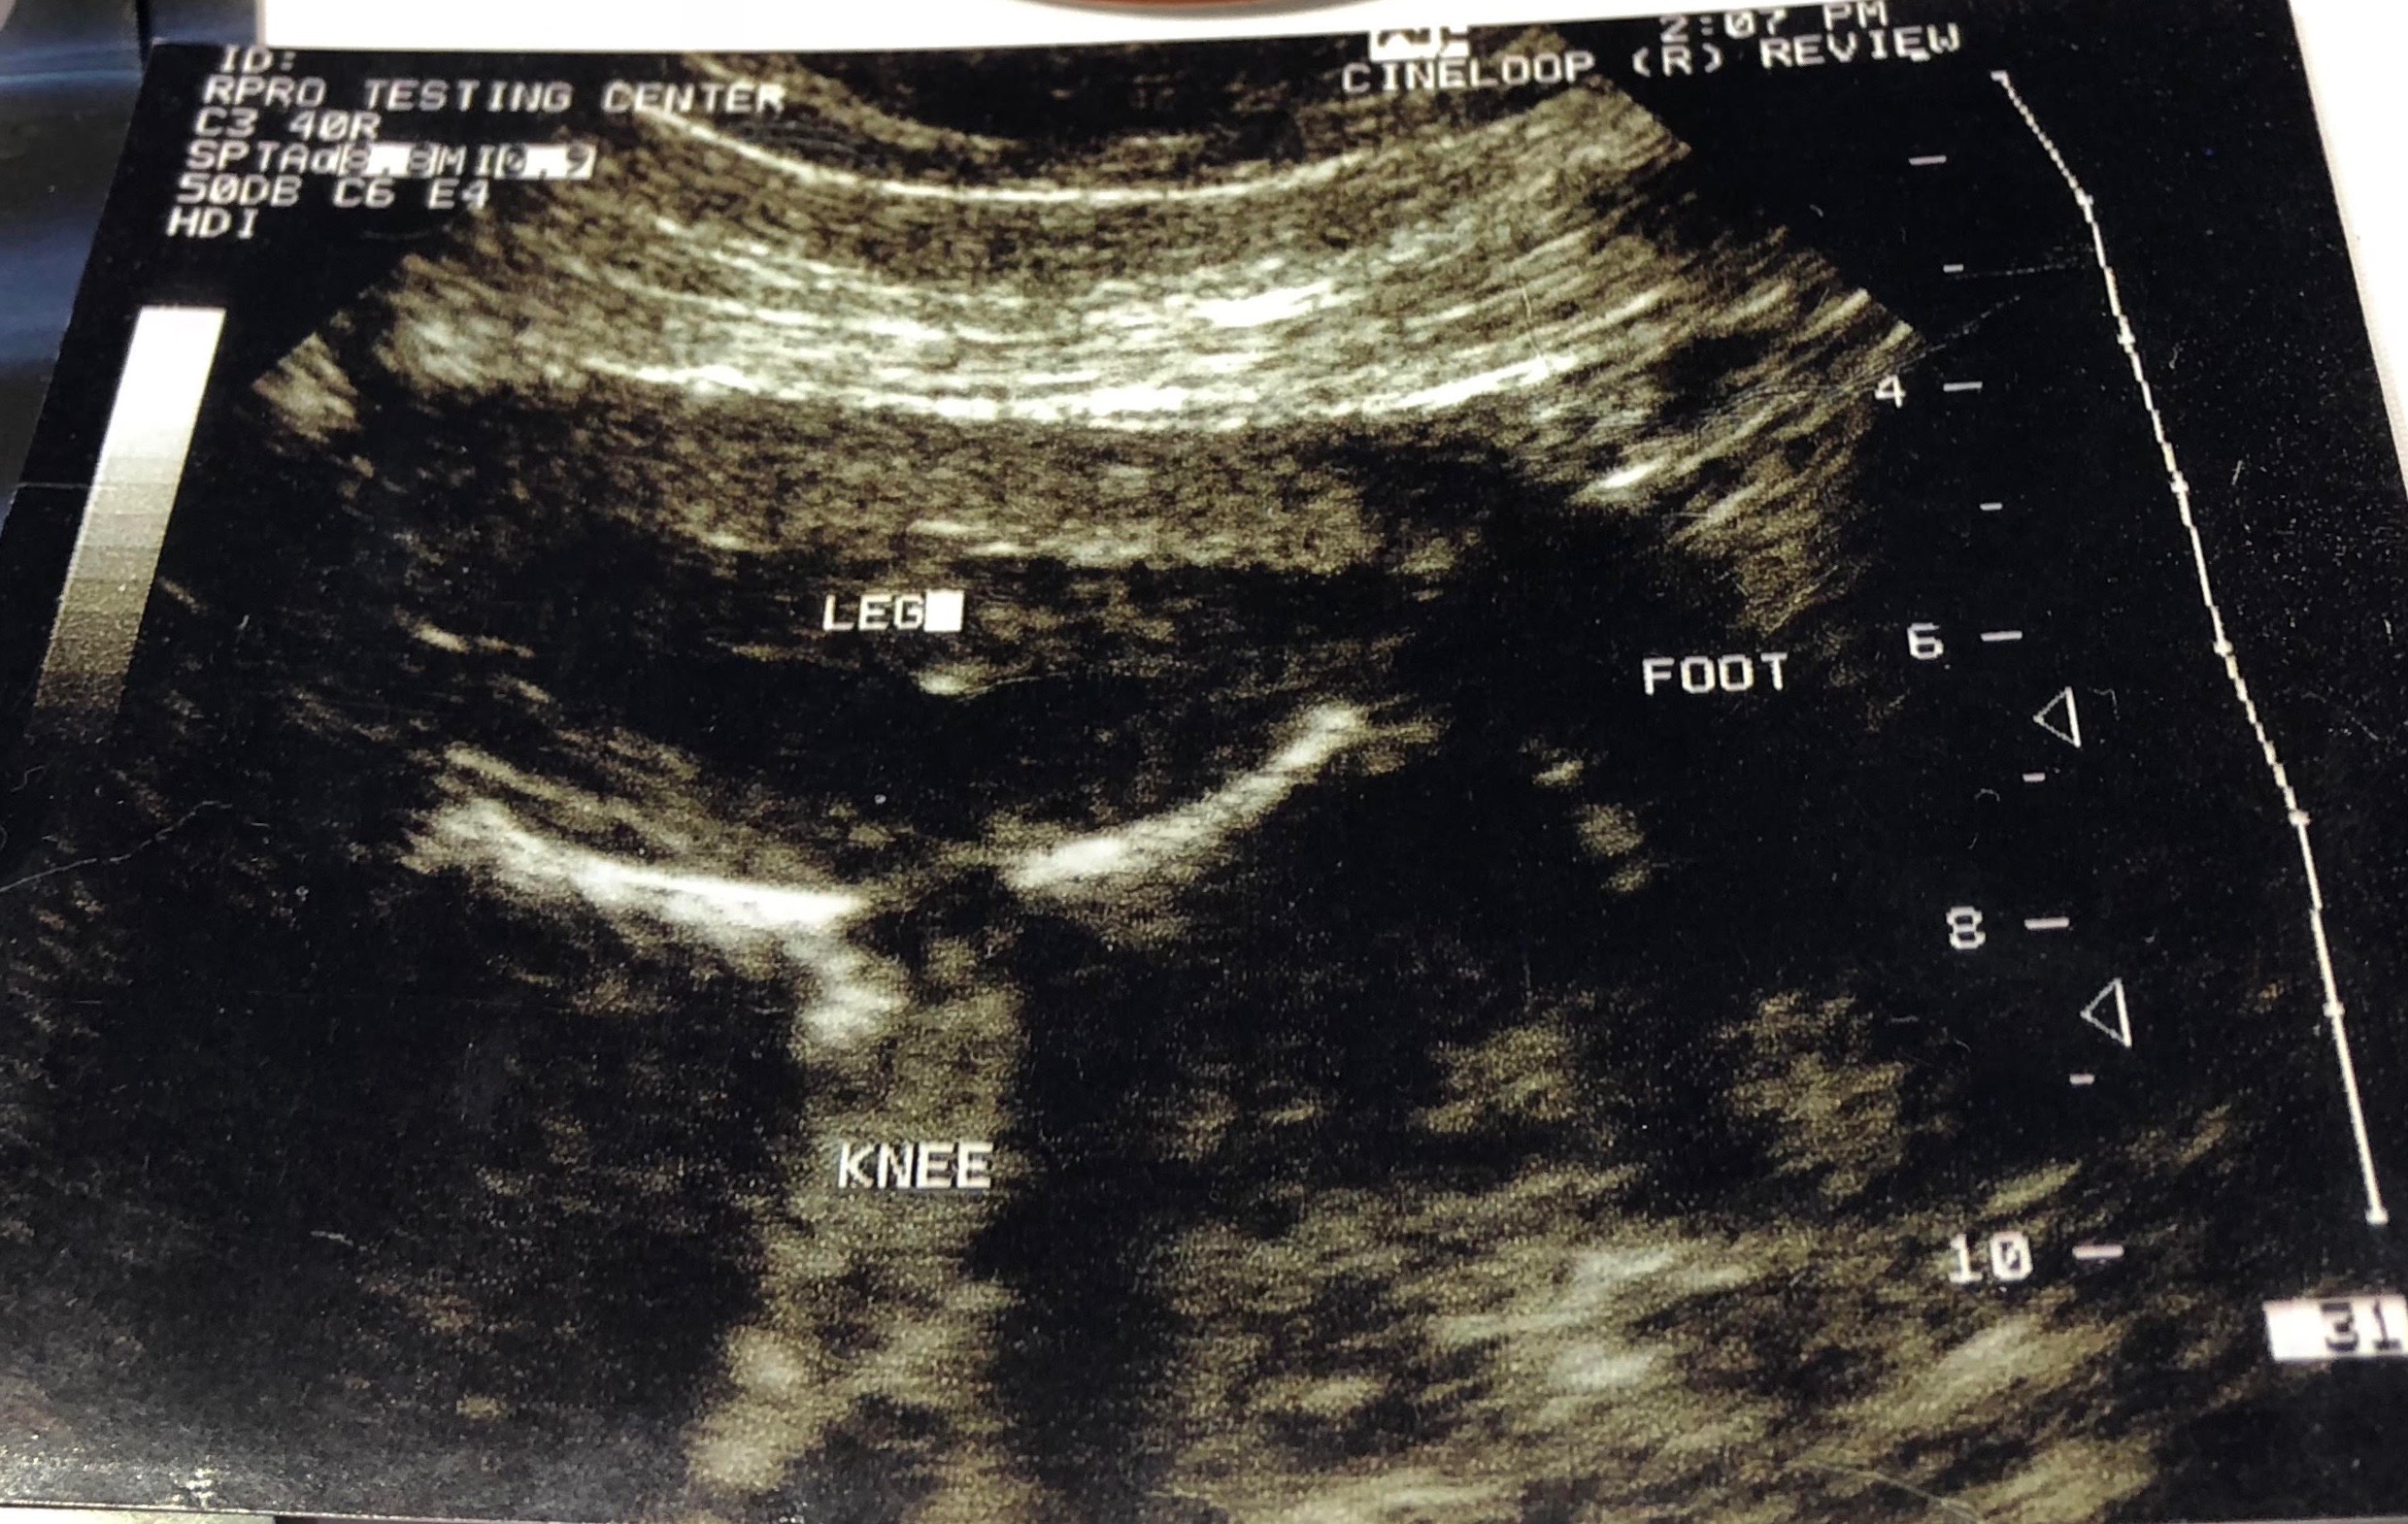

Here’s a close-up of the image: